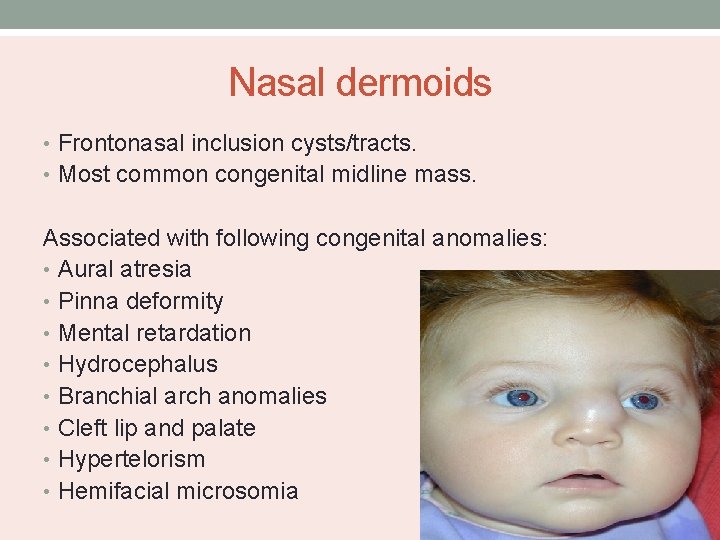

Nasal dermoids • Frontonasal inclusion cysts/tracts. • Most common congenital midline mass. Associated with following congenital anomalies: • Aural atresia • Pinna deformity • Mental retardation • Hydrocephalus • Branchial arch anomalies • Cleft lip and palate • Hypertelorism • Hemifacial microsomia